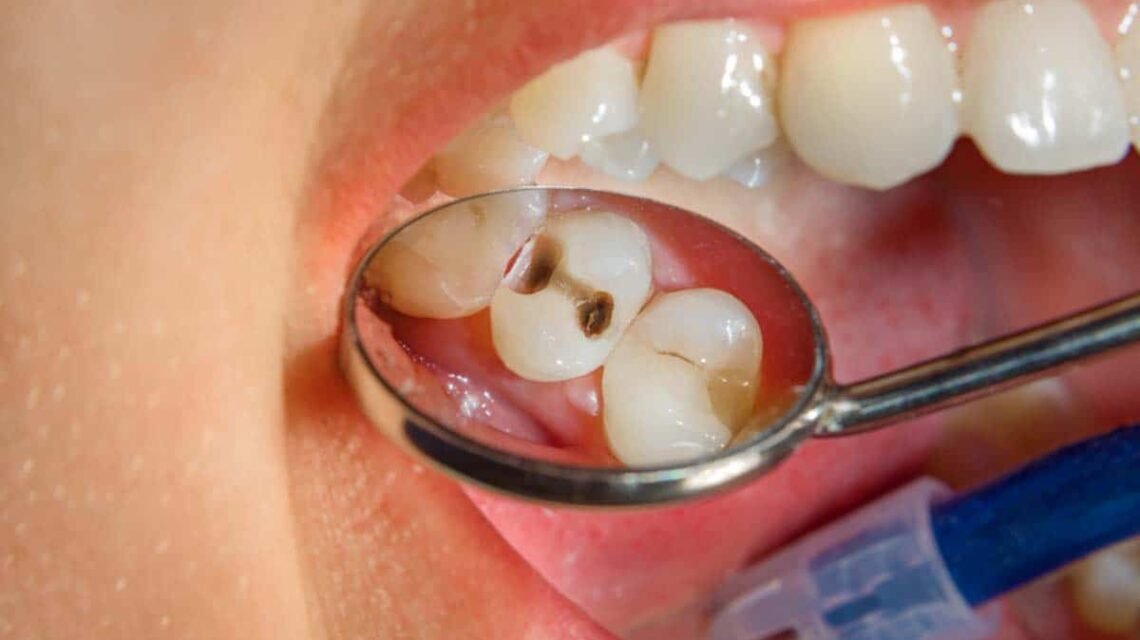

Los posibles efectos negativos de las deficiencias de vitaminas y nutrientes pueden hacer que el cuerpo se apague y no funcione correctamente y eso también se reflejará en la boca. Los signos orales reveladores de los trastornos alimentarios incluyen:

– La caries dental

Además de la erosión a través del ácido del estómago, también podrán detectar cosas como la caries dental por el consumo excesivo de azúcar y signos de deficiencias de nutrientes.